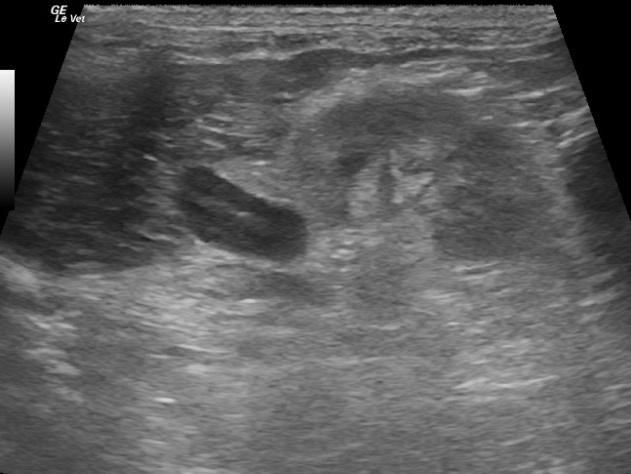

A 5-year-old FI Guinea Pig was presented with history of flank alopecia and weight loss. CBC was within normal limits. The only abnormality on blood chemistry was a slight ALT elevation.